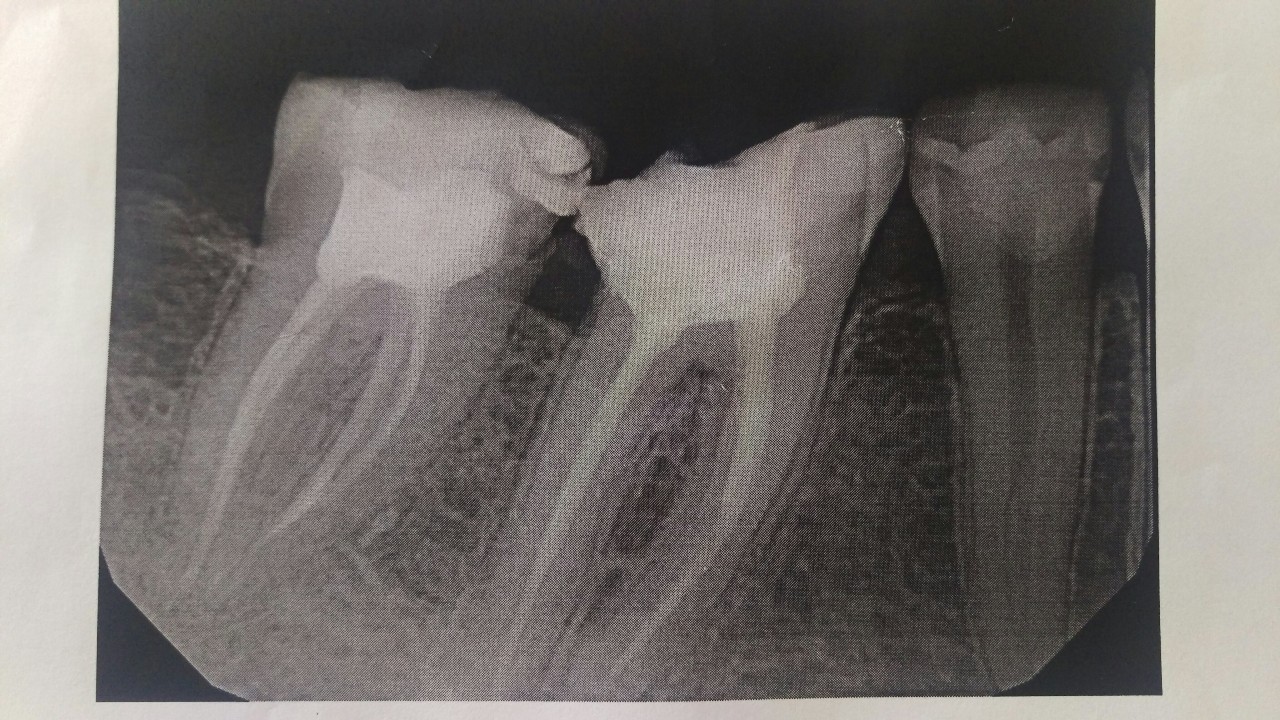

Рентгеновские снимки кариеса корня зуба

Раздел: Визуальные уроки